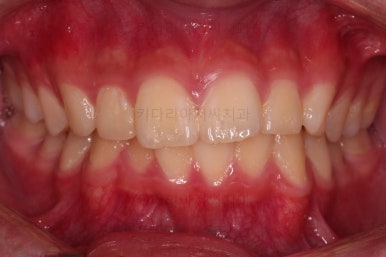

초진 때의 입 안의 모습이에요.

집 근처 치과에서 어금니가 나와야되는데 보이지 않는다는 말씀을 듣고 찾아오셨어요.

치열이 조금 삐뚤긴 하지만 교정치료는 크게 관심이 없었던 환자분이었어요.

밥 먹는 것도 크게 불편함이 없었고요.

대신, 우측 아래 화살표를 보시면 나와야 될 어금니가 나오지 못하고 있는 상황이었어요.

얼굴모습은 양호했고요 웃을 때 드러나는 치열이 약간 삐뚤었지만 교정치료는 원하지 않으셨어요.